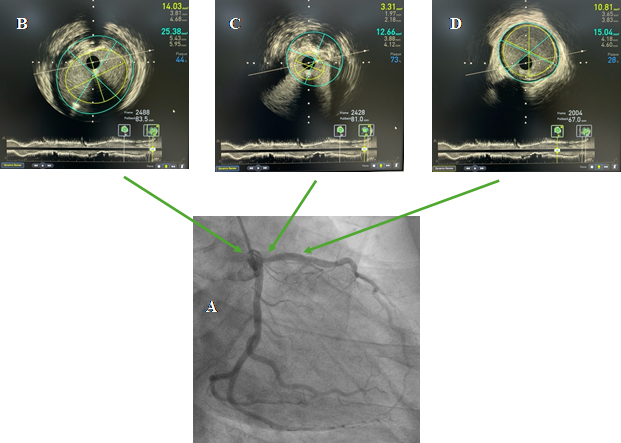

Can thiệp động mạch vành qua da đã trở thành phương pháp điều trị được lựa chọn đối với bệnh nhân hẹp nặng động mạch vành. Hiện tại, can thiệp động mạch vành qua da chủ yếu được thực hiện dưới sự hướng dẫn của máy DSA. Tuy nhiên, các phương tiện hình ảnh học trong lòng mạch vành được sử dụng ngày càng nhiều để tối ưu hoá kết quả can thiệp, cũng như hỗ trợ can thiệp đối với các tổn thương phức tạp như tổn thương thân chung động mạch vành trái, tổn thương chỗ chia đôi, tổn thương vôi hoá... Vừa qua, Đơn vị DSA, Trung Tâm Tim Mạch đã thực hiện kỹ thuật Siêu âm trong lòng mạch (IVUS), là kỹ thuật hình ảnh nội mạch cho phép quan sát trực tiếp cấu trúc thành mạch và đặc điểm mảng xơ vữa, trong can thiệp động mạch vành, giúp chuẩn bị tổn thương cũng như tối ưu hoá kết quả can thiệp.